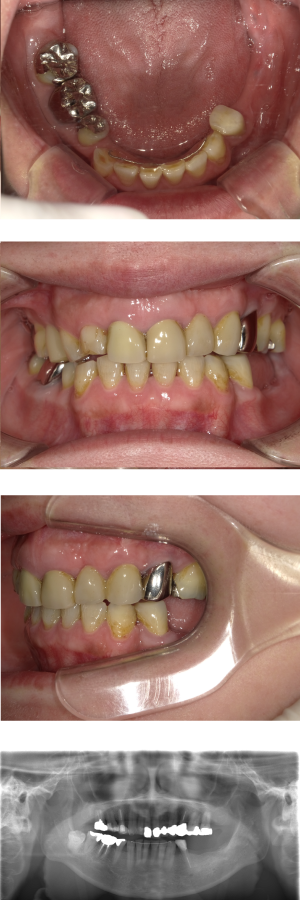

30代 女性 奥歯 インプラント

| 年代・性別 | 30代・女性 |

| 治療回数 | 10回(術前治療・検査除く) |

| 治療期間 | 約1年 |

| 料金 | ¥410,300(税込)※別途検査料 |

失った歯を補うために、インプラント治療は優れた治療方法です。 しかし、全ての人にインプラント治療が優れている治療ではありません。 |

| 副作用 | 術後に腫れ・痛みが出る可能性がある。 |